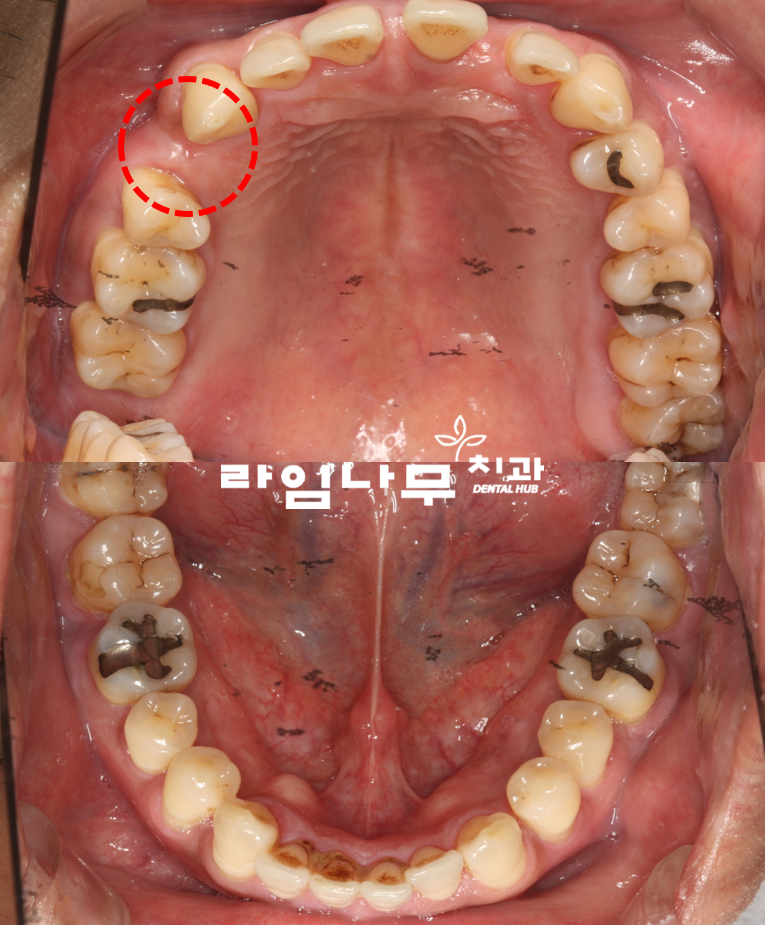

치아 전체적으로 할 치료가 많아요..

라는 주소로 임플란트 상담을 원하셨던

환자분의 첫 진단 사진입니다.

치아 사이가 굉장히 많이 벌어져있죠?

환자분의 경우 치아를 잡아주는 잇.몸의 문제,

즉 치.주질환으로 인해 제 자리에 치아가 유지 되지 않았으며

치.아가 전체적으로 흔들리며 잇.몸.뼈의 상태가 좋지 않았습니다

특히 위쪽의 사진의 빨간색으로 표시된 부분의 경우는

이미 자연적으로 발치가 된지 시간이 지났기 때문에

잇.몸.뼈가 푹 꺼진 것이 보이시죠?